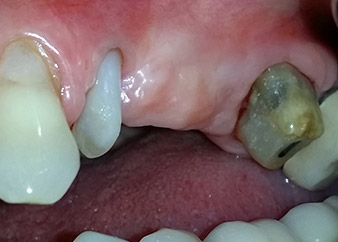

Eine 58-jährige Patientin, die auch eine gute Freundin und ärztliche Kollegin ist, beschwerte sich über Schmerzen und erhöhte Beweglichkeit ihres Brückenpfeilers 24. Es lag auch eine parodontale Entzündung vor, mit Taschentiefen von 7 mm mesiobukkal und mehr als 12 mm distal und einer Furkationsbeteiligung dritten Grades. Darüber hinaus zeigte die Röntgenaufnahme eine großflächige apikale Aufhellung am endodontisch (alio loco) vorbehandelten Zahn 24 (Abb. 1).

Ein Jahr zuvor waren die Zähne 25 und 26 vor dem Einsetzen der Brücke aufgrund traumatischer und endoparodontaler Ursachen extrahiert worden. Eine Paro-Endo-Läsion wurde bei unklarer ätiologischer Hauptkomponente für den Zahn 24 diagnostiziert. Die Patientin machte deutlich, dass sie ihre Pfeilerzähne 24 und 27 behalten und keinen endgültigen oder temporären herausnehmbaren Zahnersatz akzeptieren will. Darum wurde vereinbart, alles zu versuchen, beide Zähne, trotz der nach den radiologischen und klinischen Befunden als schlecht einzustufenden Prognose, zu erhalten.

Außerdem wurde die Platzierung zweier verdeckt einheilender Implantate an den Positionen 25 und 26 bei einem chirurgischen Eingriff mit offenem parodontalen Debridement und Wurzelspitzenresektion am Zahn 24 geplant. Aufgrund des vertikalen Knochendefizits im Implantationsbereich wurde auch eine interne Sinusbodenaugmentation geplant.